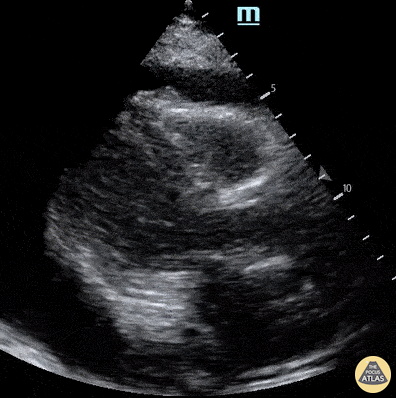

Seen here is a parasternal long axis view of a patient with cardiac tamponade. Francisco Norman

https://www.thepocusatlas.com/pericardial-disease